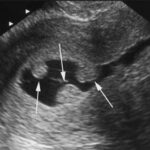

این اصطلاح در واقع حالتی است که در سونوگرافی مثانه صداهای غیرطبیعی وجود دارد. تودههای لخته خون و اثرات بهجایمانده از عفونتهای ادراری ازجمله ذرات اکوژنیک هستند که در سونوگرافی مشخص میشوند.

وجود ذرات معلق در ادرار میتونه علل متعدد داشته باشه مثل عفونت یا رسوبات ادراری ناشی از غلیظ بودن ادرار یا ذرات تشکیل دهنده سنگ. که این واژه به تنهایی اهمیتی ندارد و در کنار دیگر علائم و شرح حال فرد هست که تفسیر می شود. مصرف زیاد مایعات و ورزش میزان آن را کم می کند همچنین وجود ذرات اکوژن میتونه به علت بالا بودن املاح ادرار،کم آبی،عفونت صورت می گیرد.